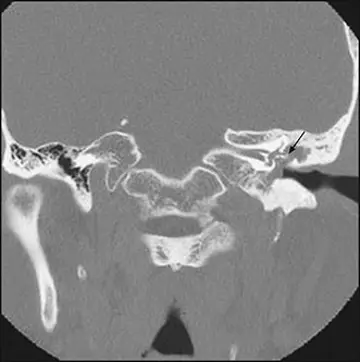

غشای تمپانیک سوراخ و شریان